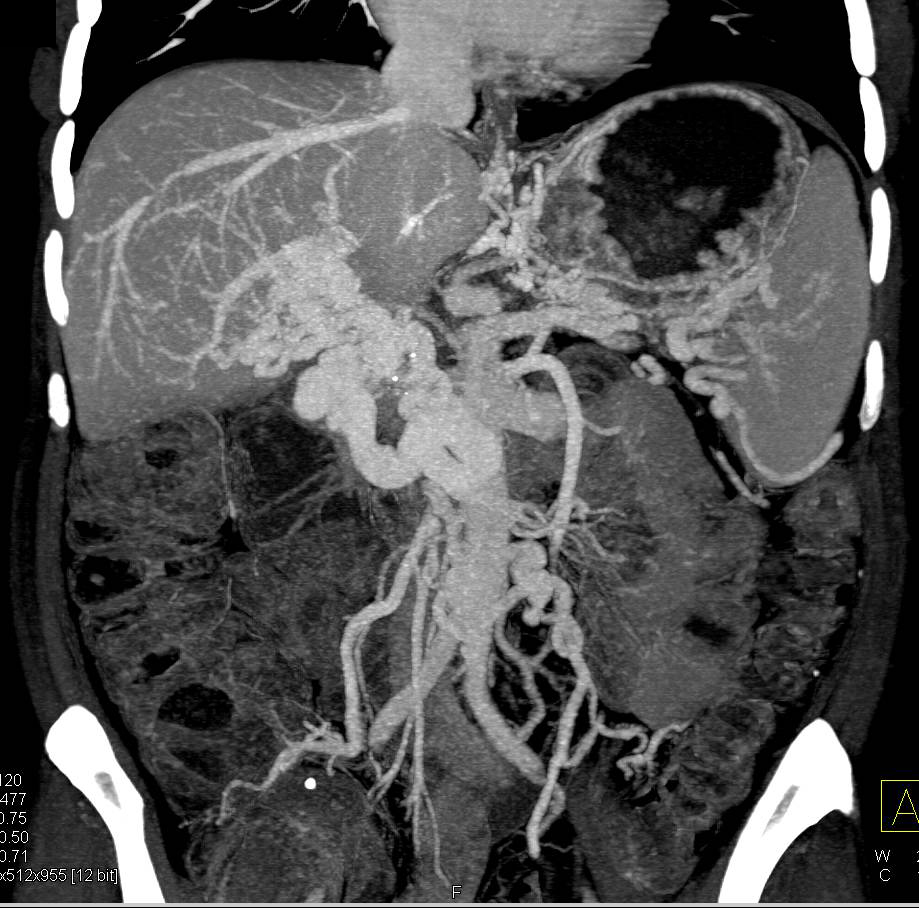

Hydatid Disease